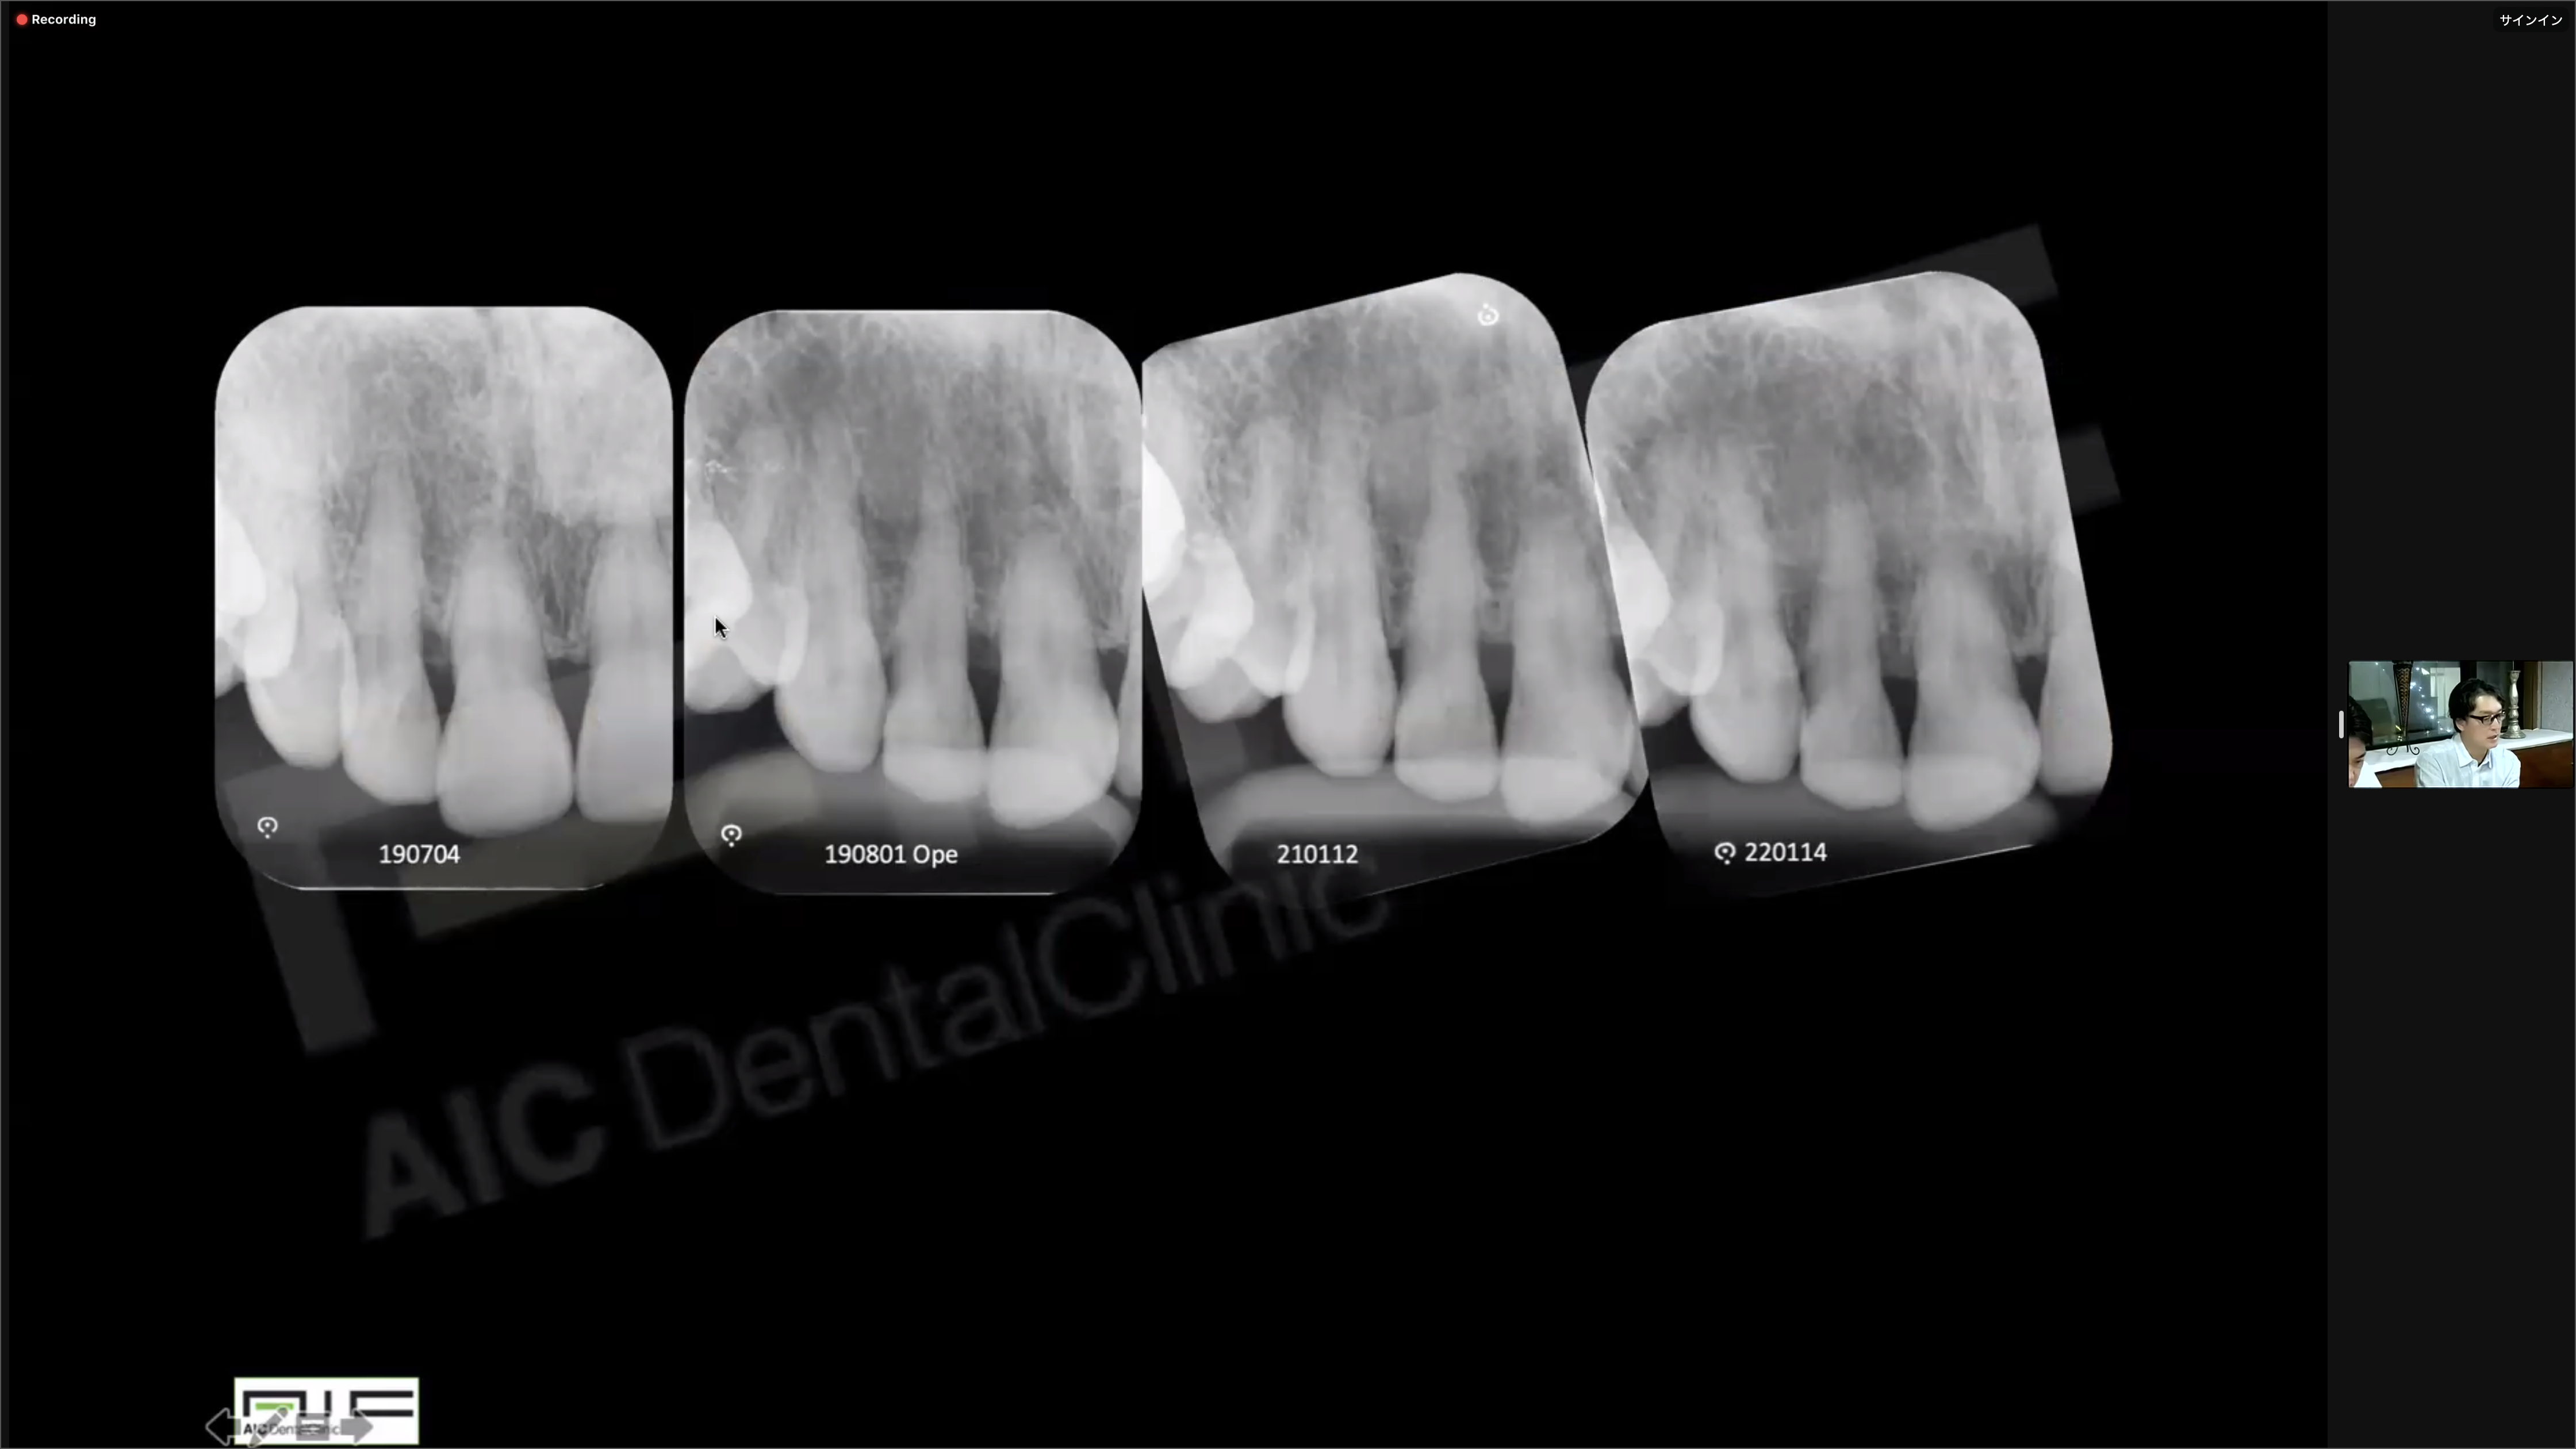

下記のようなOPE術式の流れなど一連の座学を受講しました。右上2遠心部の歯槽骨が再生されているのがわかります。